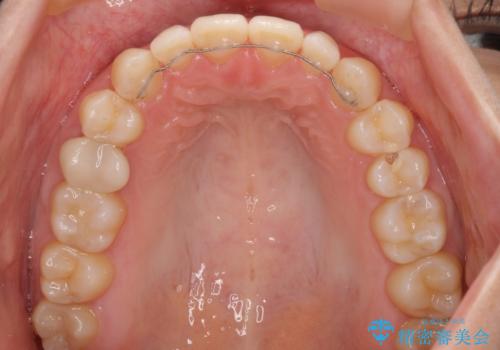

空隙歯列(すきっ歯)は、舌の突出癖をある程度改善できたとしても、後戻りにより隙間が開きやすいと言われています。

裏側から細いワイヤーで保定するとともに、睡眠時のマウスピース装着を徹底していただくことで、後戻りを最小限にとどめます。